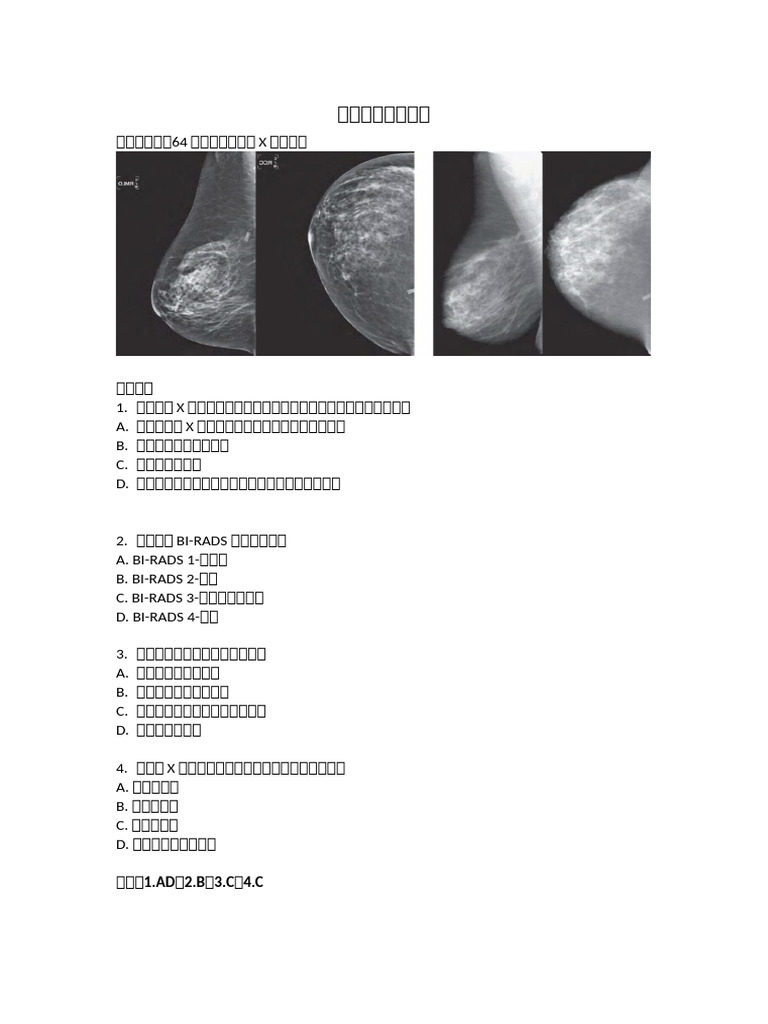

» Bi rads 2 是 什麼 意思 (97) 사진

Bi rads 2 是 什麼 意思 (97) 사진